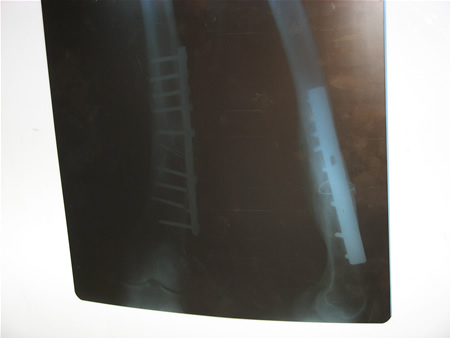

![]() 术前董连文的骨折部位的拍片